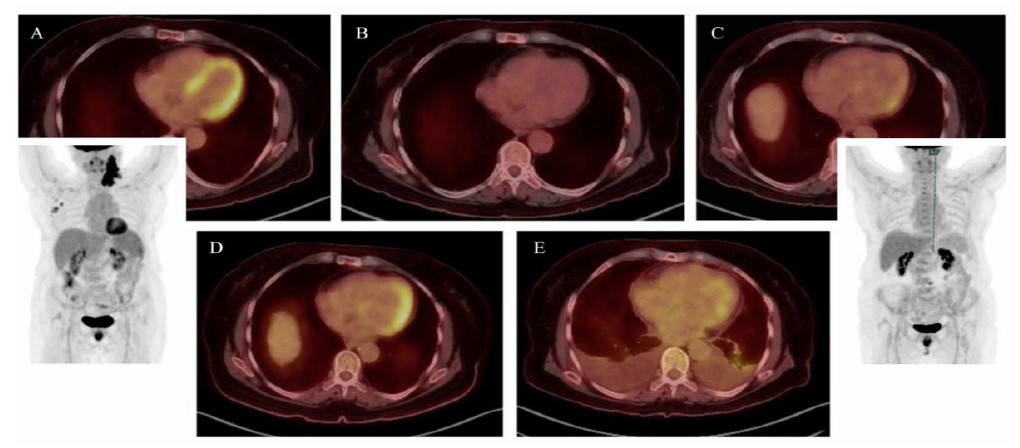

A retrospective case review revealed peaks in acute-phase reactants, eosinophilia, and β2-microglobulinemia prior to chemotherapy, with transient normalization following tumor response and a subsequent rise at the time of cardiac disease onset (Fig. 5). In five consecutive PET-CT scans conducted to monitor her oncologic disease, signs indicating myocardial inflammation were observed, aligning with spikes in laboratory markers (Fig. 6). Taken together with the highly suggestive cardiac CMR findings, these results support a probable diagnosis of paraneoplastic EM known in its thrombotic phase as Loeffler endocarditis, within the context of cHL, and likely worsened by doxorubicin-based chemotherapy.

Sequential PET-CT axial and volumetric reconstructions during patient follow-up, demonstrating: (A) the active phase of Hodgkin’s lymphoma with prominent, widespread myocardial uptake (late 2021); (B) following initial chemotherapy cycles, a complete oncologic response with no myocardial uptake (early 2022); (C) several months after finishing chemotherapy, revealing early signs of myocardial uptake while the patient remained asymptomatic from a cardiovascular perspective (late 2022); (D) the onset of clinical heart failure, exhibiting intense, asymmetric uptake corresponding to areas of increased gadolinium enhancement on CMR (mid 2023); (E) end-stage cardiomyopathy, showing relatively decreased and patchy uptake, consistent with established myocardial fibrosis (mid 2024, two months before the patient’s passing).